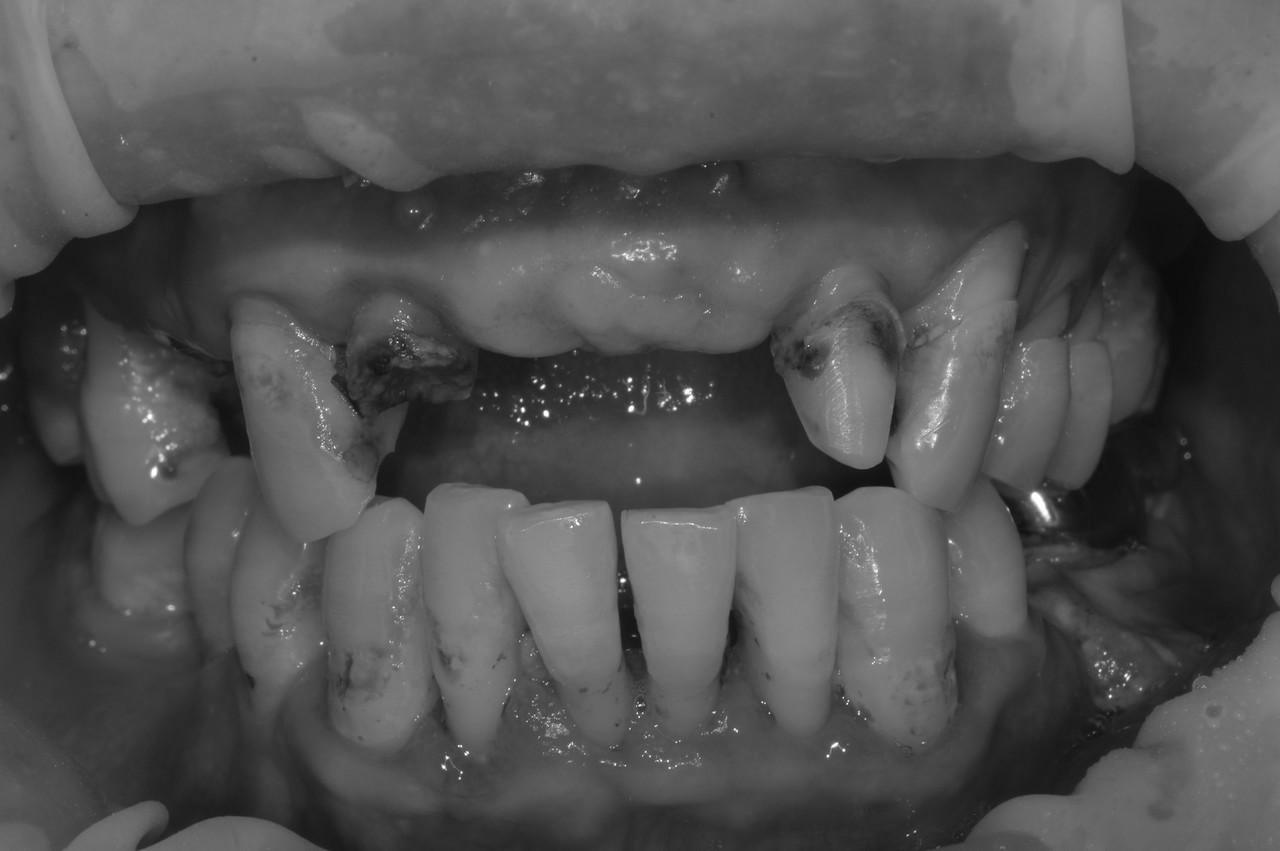

치아우식, 신경치료 및 치은성형술, 심미보철치료

치료 기간 2023. 11. 02 ~ 2023. 12. 20

확장 개원 후 마무리하신 환자분입니다. 앞니 기존 보철물을 하고 계셨지만 치아가 삭아서 보철물이 탈락해서 내원하셨습니다.

환자분께서는 뽑고 임플란트를 생각하고 오셨지만... “치아는 살릴 수 있다면, 살리는 게 좋다.”

간단한 잇몸 수술, 신경치료 후에 기둥을 세워 치아머리만 만들어진다면 충분히 살릴 수 있다고 판단하고 살리는 쪽으로 설명드렸습니다.

환자분들의 치아 하나하나를 소중히 생각하는 참조은치과입니다.

* 상기 사진은 본원 권대근 대표원장이 치료한 환자분의 동의를 받은 이미지 사진으로 실제와 차이가 있을 수 있습니다.